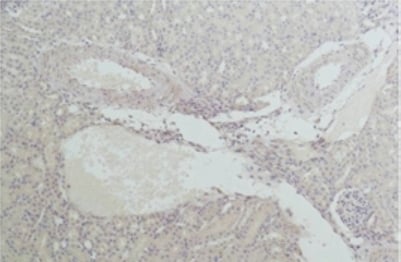

IHC (Immunohiostchemistry)

(Immunohistochemistry of paraffin-embedded Mouse kidney tissue using Nrf2 Polyclonal Antibody at dilution of 1:200.)